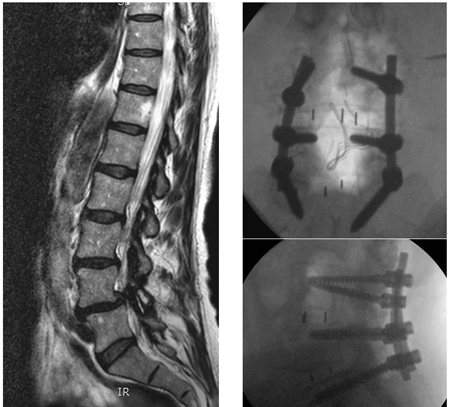

[Figure caption and citation for the preceding image starts]: Spondylolisthesis: flexion/extension viewsFrom the collection of Dr N. Quiraishi [Citation ends].

[Figure caption and citation for the preceding image starts]: Preoperative MRI sagittal T2 sequenceFrom the collection of Dr N. Quiraishi [Citation ends].

[Figure caption and citation for the preceding image starts]: Intra-operative images showing a gradual reduction of the deformity: L4 to S1 instrumented fusion, transforaminal fusion at L5S1 and bilateral L5 decompressionFrom the collection of Dr N. Quiraishi [Citation ends].

[Figure caption and citation for the preceding image starts]: Postoperative radiographsFrom the collection of Dr N. Quiraishi [Citation ends].